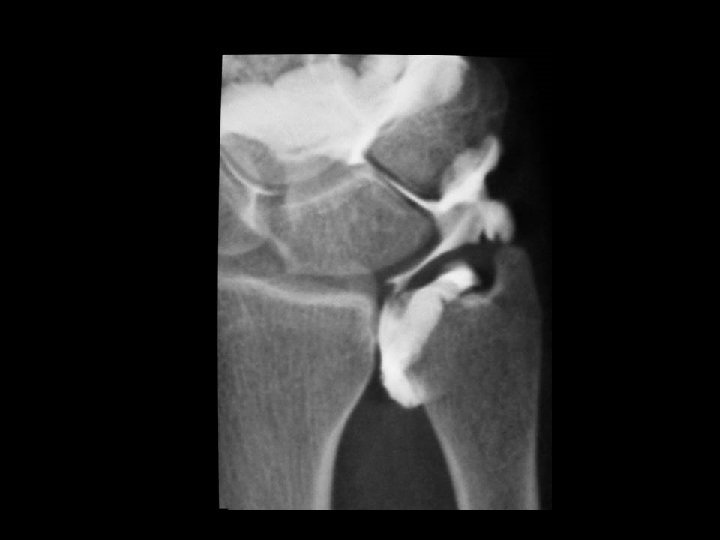

Lunotriquetral Dissociation • Like the scapholunate interosseous ligament, disruption may be either traumatic or degenerative. • Many tears associated with Palmer II TFCC tears. • Studies and literature regarding this ligament is scarce and controversial. • Occur both in isolation or part of the perilunate instability.

Lunotriquetral Dissociation • Heterogeneity of clinical symptoms from asymptomatic tears to collapse of the carpus with a fork-like deformity of the wrist. • Generally pain aggavated with ulnar deviation. • Sensation of weakness or instability.

VISI PATTERN LUNATE is the intercalated element